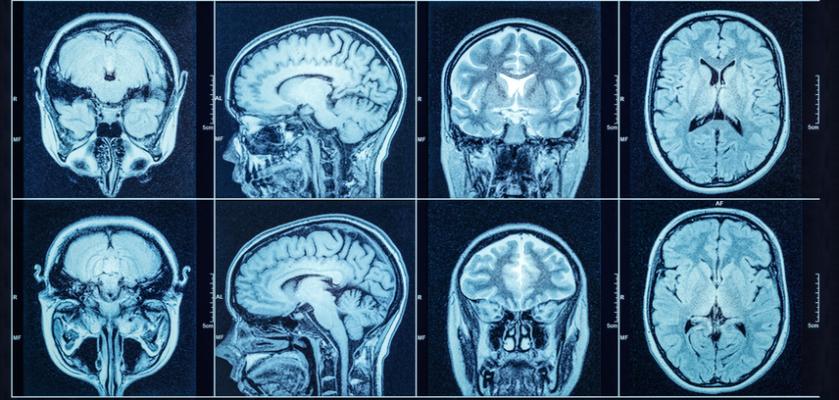

August 25, 2021 — When patients exhibit stroke symptoms, doctors must quickly make a life or death determination: Are their symptoms caused by a clot that can be treated with blood thinners or by bleeding in the brain, which may require surgery? A new Yale-led study shows that a portable magnetic resonance imaging (MRI) device can help identify such intracranial hemorrhages, potentially life-saving information particularly in areas or scenarios where access to sophisticated brain imaging scans are not readily available.

Neuroradiologists interpreting images acquired by Hyperfine’s portable MRI correctly identified 80% of intracerebral hemorrhages.

The study is the first to validate the appearance and clinical implications of a brain hemorrhage using a portable MRI device.